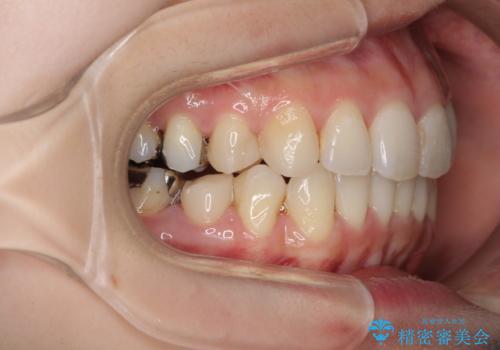

- 上下のデコボコと奥歯の咬みにくさを気にして来院された患者様です。

上顎骨の幅が下顎骨よりも小さいので、拡大装置により骨幅を広げて上下関係を改善し、その後インビザラインにて歯並びを整えることとしました。

上下の骨幅を改善したことで、スムーズに歯列矯正を行うことができました。

矯正治療中に近医で銀歯を外す治療を開始したため、治療後に奥歯の咬み合わせが不十分ですが(こちらは近医での治療により改善するとのこと)、歯列と咬み合わせが改善され、患者様には大変満足していただきました。